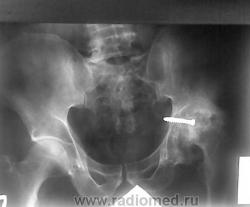

Пациенту была выполнена операция металостеосинтеза (не в нашей больнице). Ко мне снимок попал на описание, при оформлении документов для очередного продления инвалидности. У меня возник вопрос: так как шуруп выступает в просвет брюшной полости не может ли он мешать нормальному функционированию кишечника ? С подобным встречаюсь впервые.Какие будут мнения у коллег?

Видимо операция для бедных: замкнули изношенный сустав вместо протезирования. На рентгенограмме видны мягкие ткани в проекции шурупа.

В брюшную полость шуруп не проникает, так как с внутренней стороны вертлужной впадины имеется еще стенка малого таза, состоящая из мышечного слоя, слоя жировой клетчатки, и наконец, брюшины.

Кстати, и единственная кишка, которая имеется на этом уровне в малом тазу - прямая. Она, как известно, фиксирована и мало меняет свое положение.

Навскидку - m. obturatorius internus. Может, какие-либо еще, не помню. У меня, к сожалению, нет под рукой секционного атласа, могу посмотреть на досуге.

Спасибо, согласен с вами, но недостаток в том, что нет боковой проекции и мы не знаем, где шуруп по отношению к саггитальной плоскости?

Уважаемый Almo, коллега Попов абсолютно прав, хирурги тоже это знают: шуруп не вызыает никаких изменений со стороны кишечника. Я видела десятки ( а может сотни) подобных снимков после остеосинтеза или эдндопротезирования... Единственное, что он вызывает - металлоз, и это надо отметить.